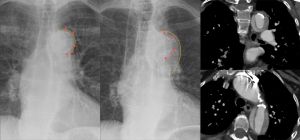

Dissection of the aortic arch: initial CXR normal visualization of the calcification shadow in the aortic arch (left); CXR 4 months later with calcification shifted centrally into the shadow of the aortic arch with a blurred external border (middle); CT scan coronal (top right) and axial (lower right).